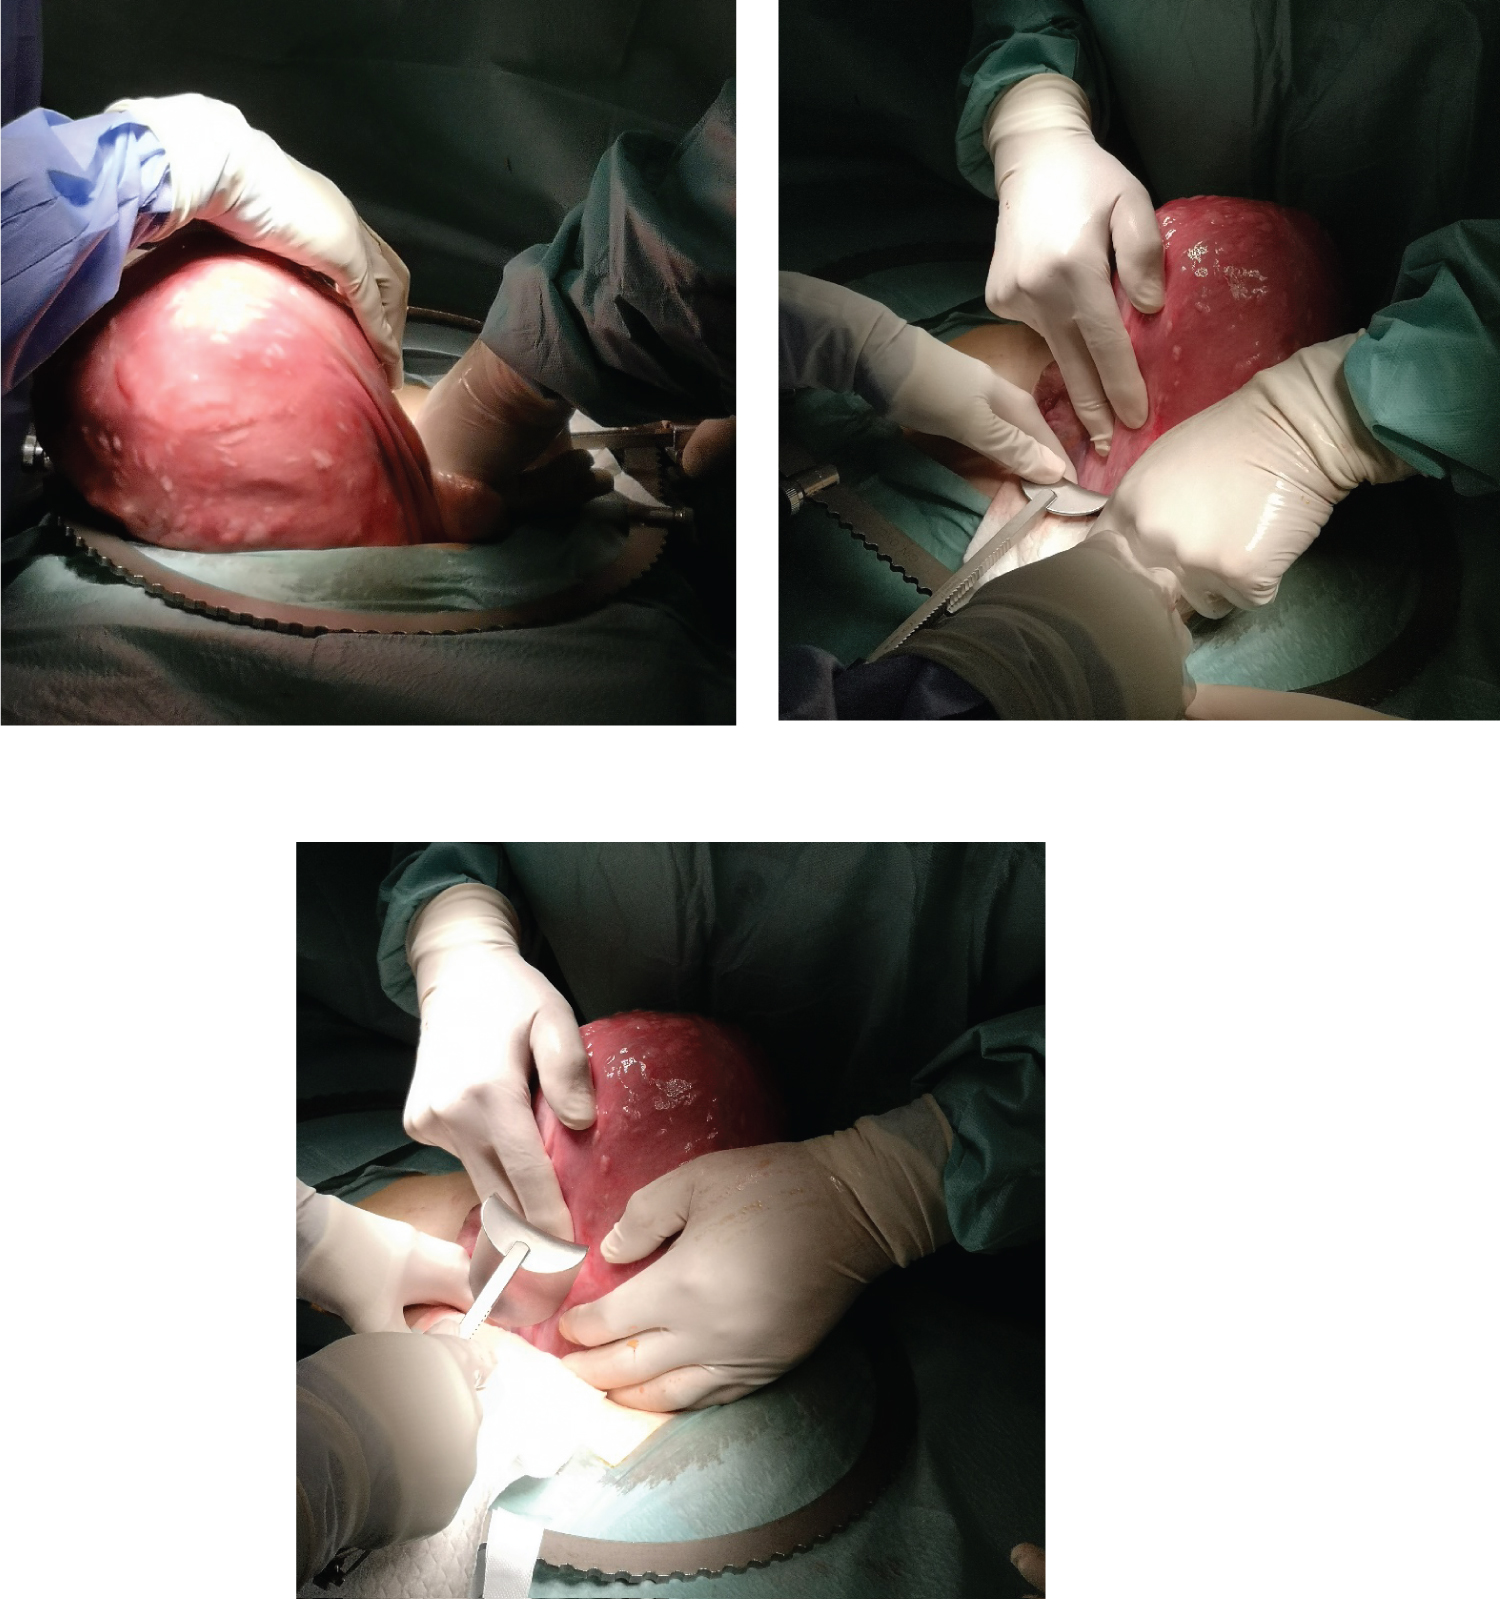

Figure 3, Figure 4 and Figure 5 show the aspect of the patient´s uterus, which weighted a total of 2900 grams. Given the size of the uterus, we decided to perform a total hysterectomy with bilateral salpingectomy. The postoperative period was uneventful.

Figure 3-5: Corresponding images of intraoperative findings.